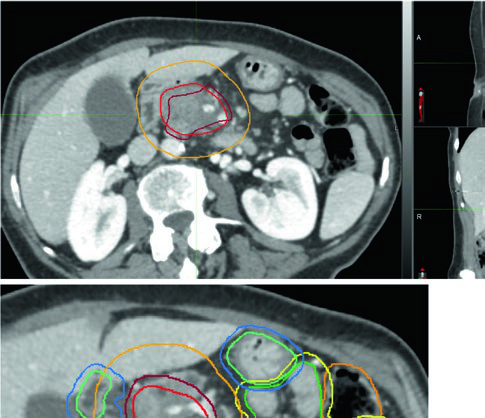

Planificación adyuvante post-pancreatectomía

El diseño de campos adyuvantes sigue el atlas de contorneo del RTOG 0848, construido alrededor de regiones de interés (ROIs) seleccionadas por facilidad de identificación y reproducibilidad. Campos más pequeños dirigidos al lecho quirúrgico, CA y AMS pueden ser apropiados en escenarios con OARs limitantes de dosis.

Volúmenes blanco adyuvantes (atlas RTOG 0848)

| Volumen | Definición y descripción |

|---|---|

| GTV | No aplica |

| CTV | Lecho quirúrgico y pancreaticoyeyunostomía (PJ) + cadenas ganglionares peripancreáticas, CA, AMS, paraaórticas, vena porta (tumores de cabeza) y esplénicas (cuerpo/cola). ROIs escalonados del RTOG 0848: • CA (1–1,5 cm proximal) • AMS (2,5–3 cm proximal) • Vena porta (VP: inicio en confluencia VMS/vena esplénica) • PJ • Aorta (superiormente al más cefálico de CA, VP o PJ; inferiormente a L2, o L3 para cubrir GTV preoperatorio) • Lecho tumoral (basado en imagen preoperatoria, informe patológico, clips quirúrgicos) |

| Expansiones | VP, PJ, CA, AMS: 1,0 cm. Aorta: 2,5–3,0 cm derecha, 1,0 cm izquierda, 2–2,5 cm anterior, 0,2 cm posterior. CTV = unión de expansiones, confirmando cobertura del lecho tumoral |

| PTV | Mínimo 0,5 cm; sin ITV en respiración libre, 1–1,5 cm craneocaudal |

Fuente: Target Volume Delineation and Field Setup, 2nd Edition (Table 16.3)